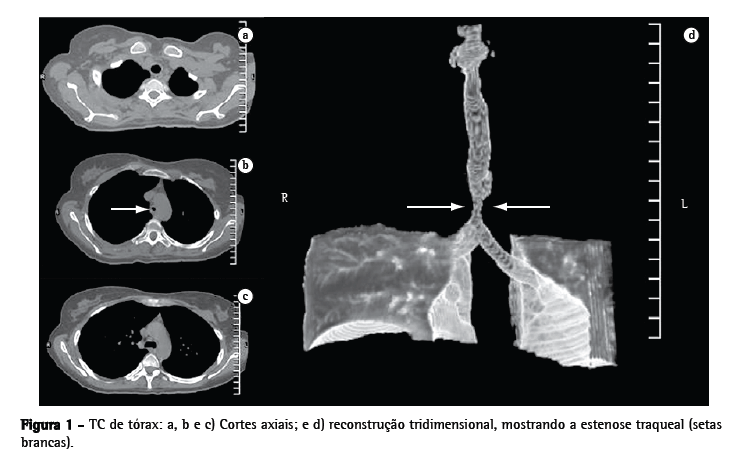

Ao exame físico apresentava estridor, além de roncos difusos. O radiograma de tórax evidenciava diminuição significativa da coluna aérea na topografia da traquéia distal. A tomografia computadorizada (TC) do tórax com reconstrução tridimensional (Figura 1) evidenciou estenose da traquéia distal (com extensão de 15 mm) 20 mm acima da carina traqueal.

A TC da via aérea foi realizada no 3º dia de pósoperatório (com retirada momentânea do TOT sob visão endoscópica), sendo obtidas as dimensões da traquéia estenosada. Tanto a reconstrução tridimensional da traquéia como suas medidas foram encaminhadas a Hood Laboratories (Pembroke, MA, EUA). Com base nessas dimensões, foi adquirida uma prótese traqueobrônquica siliconizada (tipo T-Y), compatível com a via aérea da paciente (Figura 2).